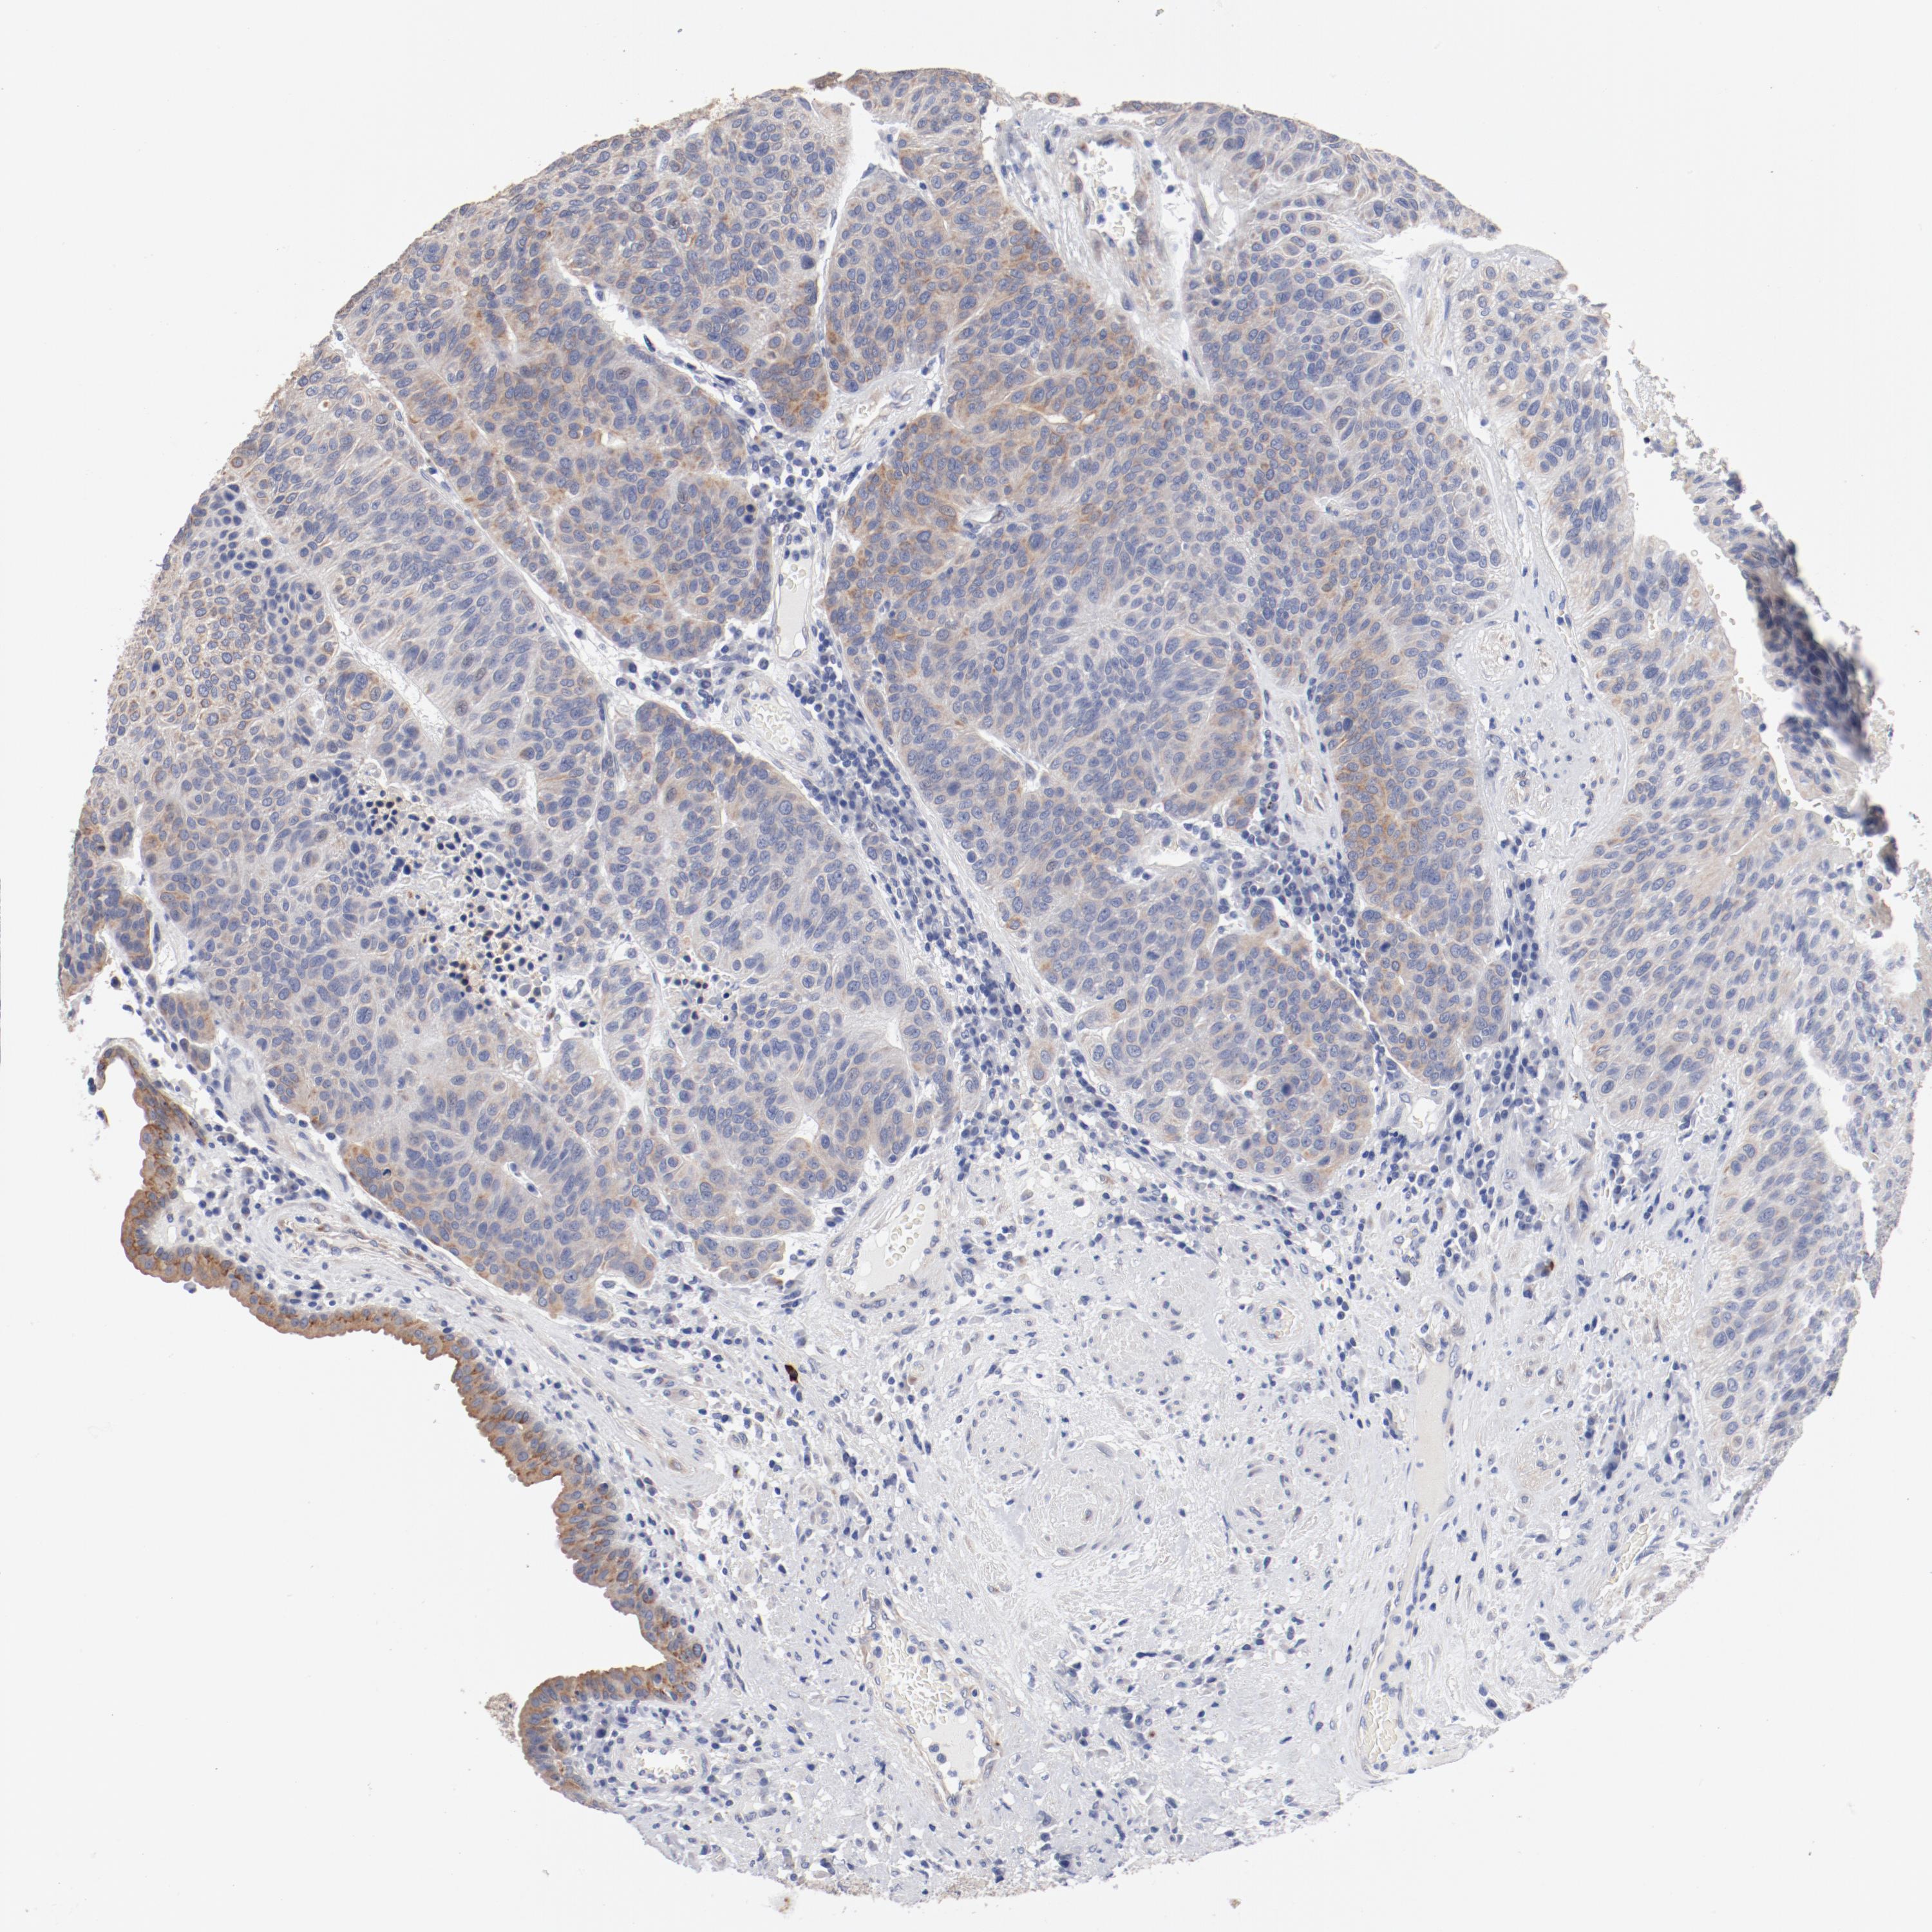

UROTHELIAL CANCER - Protein expressioni

A mouse-over function shows sample information and annotation data. Click on an image to view it in a full screen mode. Samples can be filtered based on level of antibody staining by selecting one or several of the following categories: high, medium, low and not detected. The assay and annotation is described here.

Note that samples used for immunohistochemistry by the Human Protein Atlas do not correspond to samples in the TCGA dataset.

Antibody stainingi

Antibody staining in the annotated cell types in the current human tissue is reported as not detected, low, medium, or high, based on conventional immunohistochemistry profiling in selected tissues. This score is based on the combination of the staining intensity and fraction of stained cells.

Each image is clickable and will lead to virtual microscopy that enables deeper exploration of all samples and also displays staining intensity scores, fraction scores and subcellular localization as well as patient and tissue information for each sample.

Antibody HPA003648

Staining

High

Medium

Low

Not detected

Intensity

Strong

Moderate

Weak

Negative

Quantity

>75%

75%-25%

<25%

None

Location

Nuclear

Cytoplasmic/membranous

Cytoplasmic/membranous,nuclear

Urothelial carcinoma, High grade

Urothelial carcinoma, Low grade